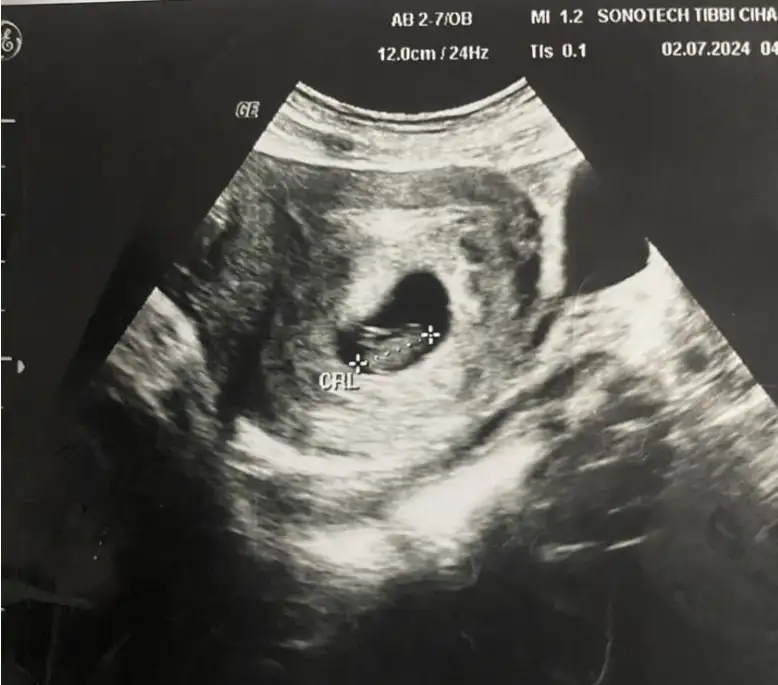

Alttan bakıldıysa kız ustten bakıldıysa erkek benceMerhaba ben Kanada’da yaşıyorum ve 8 haftalık hamileyim, keseye göre cinsiyet tahmini yapabilecek var mıdır, bu ülkede çok geç söylüyorlar şimdiden dayanamıyorum :))

Kızımın kesesine benziyor..Sağlıkla gelsinMerhaba ben Kanada’da yaşıyorum ve 8 haftalık hamileyim, keseye göre cinsiyet tahmini yapabilecek var mıdır, bu ülkede çok geç söylüyorlar şimdiden dayanamıyorum :))

Bu keseyide oğlumunkine benzettim..Sağlıkla gelsinBanada bakabilir misiniz cinsiyeti ne olabilir 10 haftalık Eki Görüntüle 3446085

Ya tipleri hepsi aynı ya kızıda erkeğide minik mercimekler...Bana doktor 12.haftada büyük hevesle erkek dedi...Eve geldim..Oğlumun ultrason görüntüleriyle karşılaştırdım hemen bu tez yanlışmış demek ki dedim(keseye göre tahmin yani) ..Gözlerimle görmek istedim..Peki bebekte erkeğe benziyor mu ben kız hissediyorum da

Kaç haftalık? Ve alttan mı ustten mı bakıldı?Cinsiyet tahmini yapar mısınız

8 haftalık karnımdan. BakıldıKaç haftalık? Ve alttan mı ustten mı bakıldı?